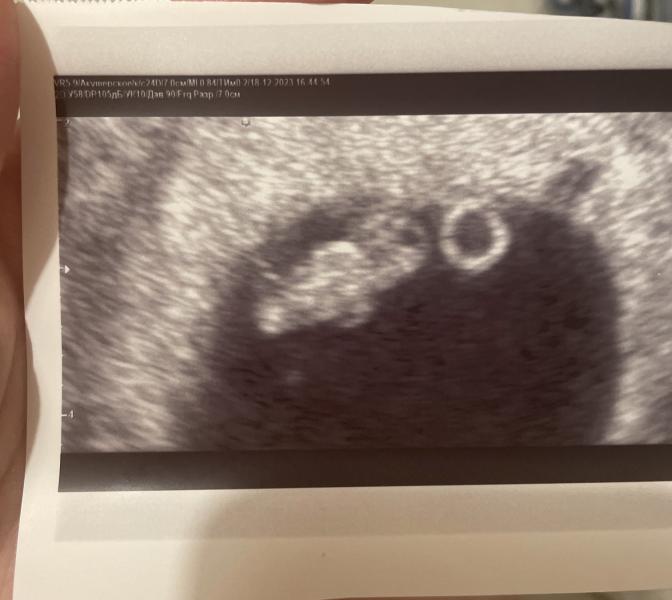

8,1 неделя по УЗИ, а по месячным 9,1: в чем разница и что это значит для будущей мамы?

post image

Встала на учет😍

8,1 недель по узи .

По месячным срок 9,1.

18.12.2023